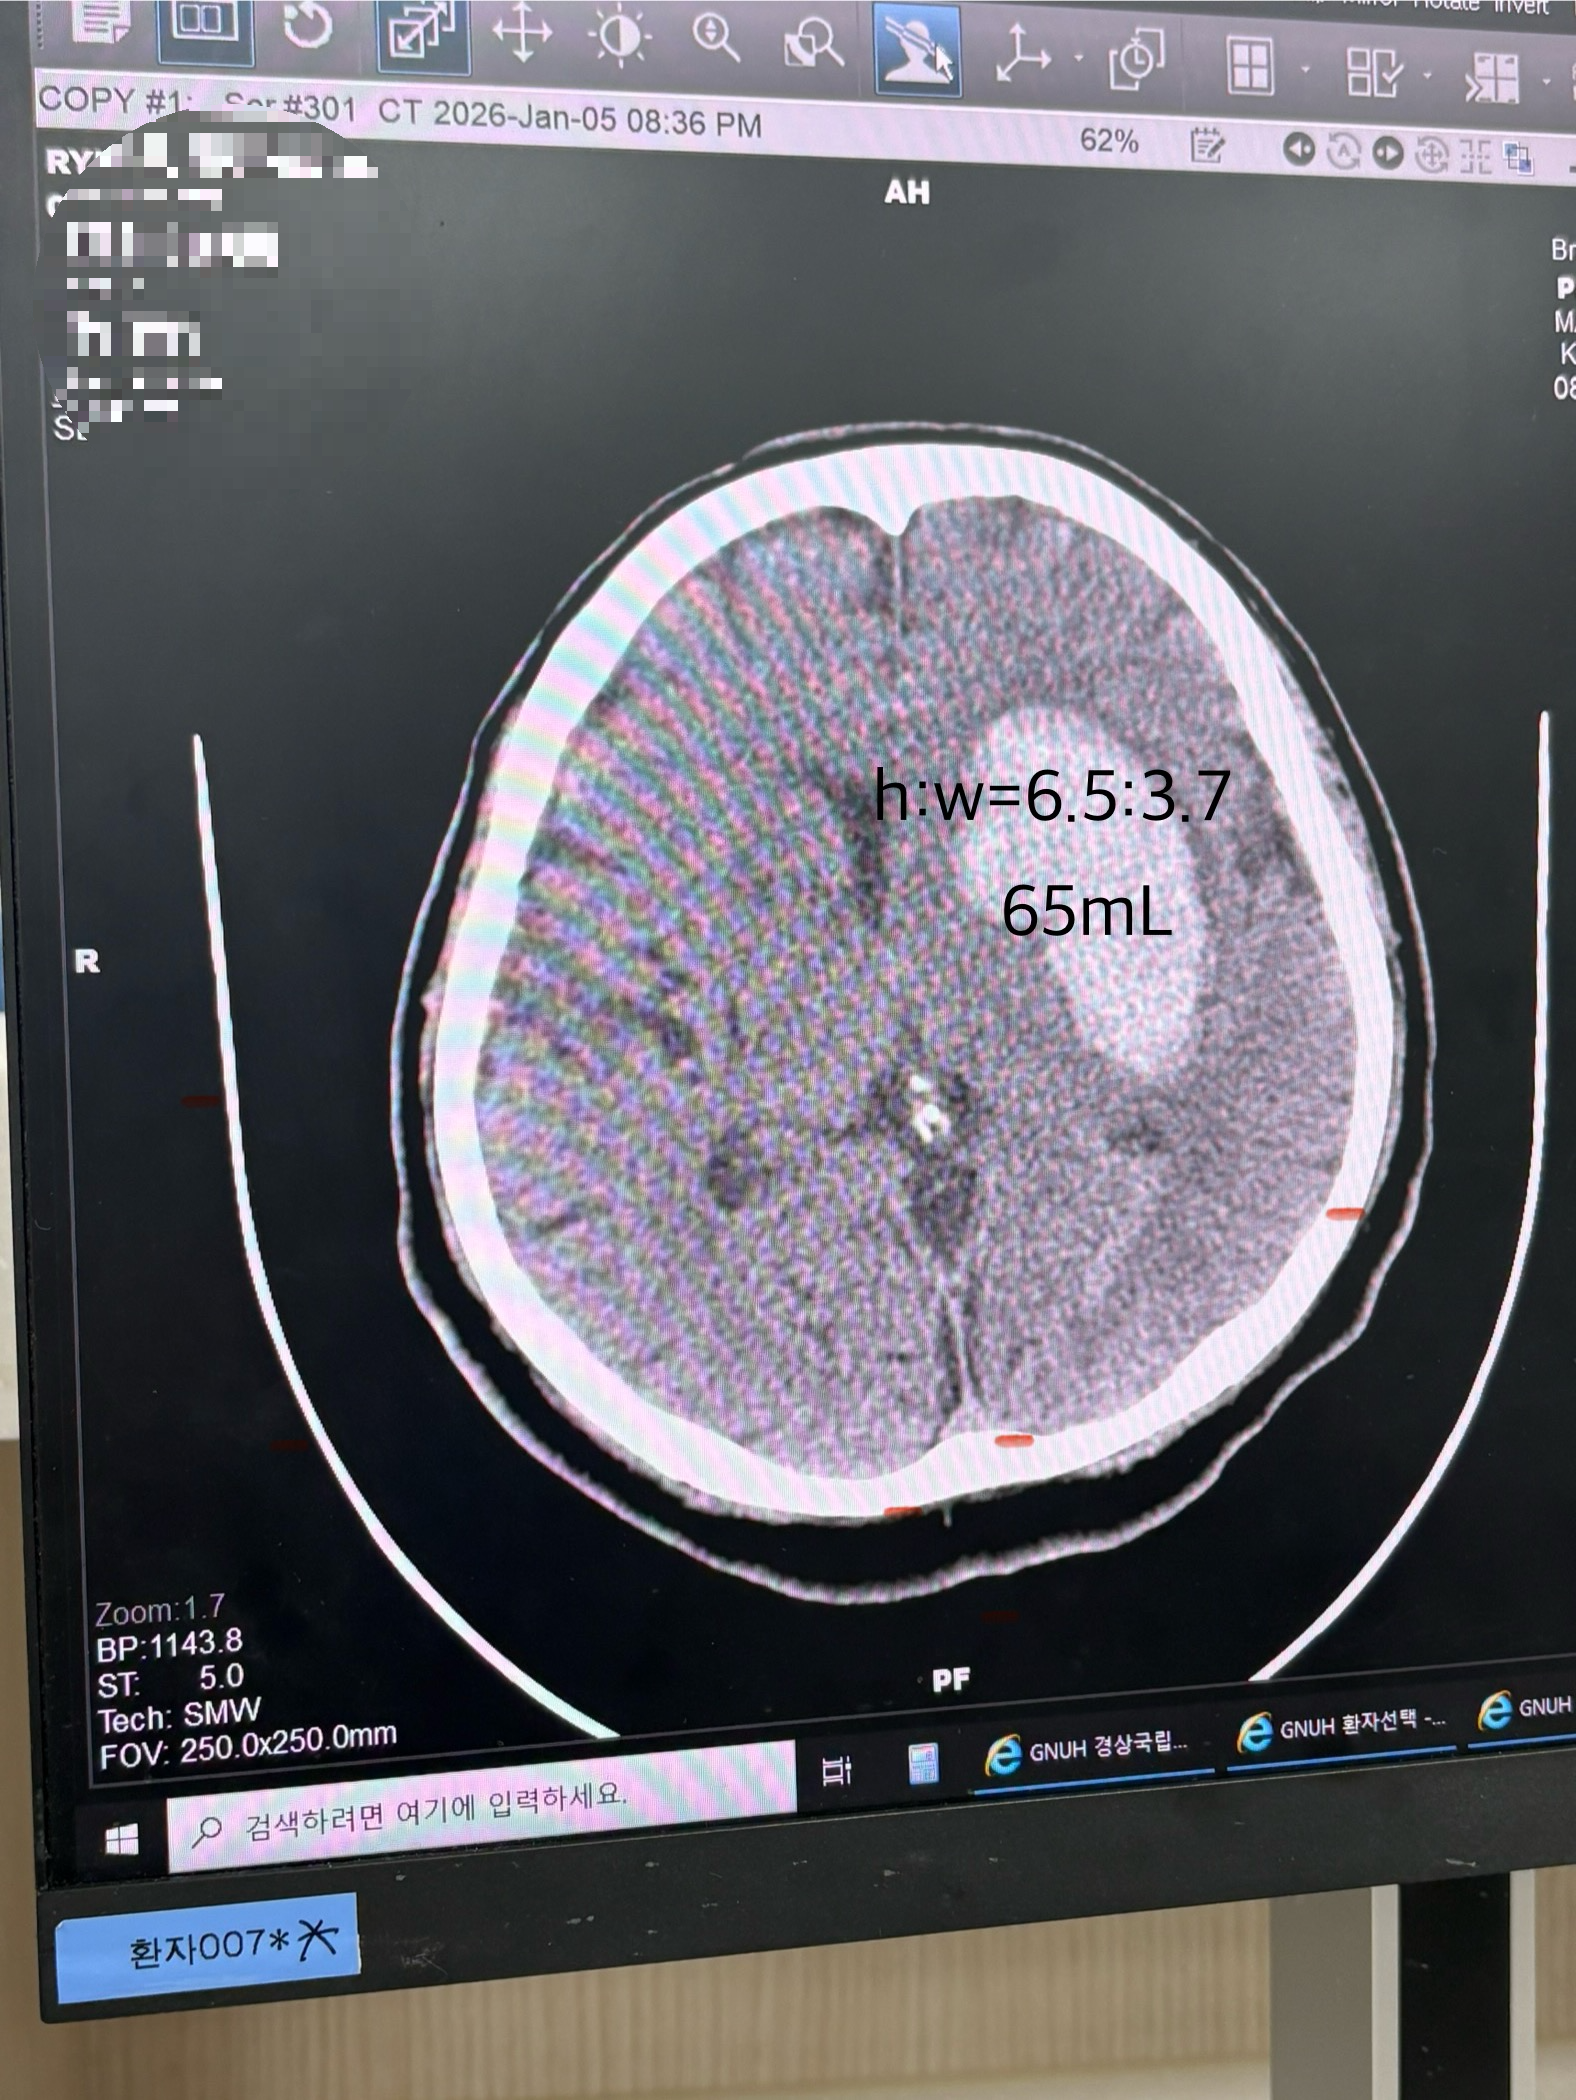

세로 6.5cm, 가로 3.7cm, 혈종 용적이 65mL로 운동 능력과 인지 일부, 시상 영역도 일부 포함됐다.

혈종이 시상 영역까지 침범했기에 의식이 회복되기까지의 시간이 길어질 수 있다고 한다.

고비는 뇌에서 혈종을 빼고 난 후 부종을 가라앉히는 시기로, 약물로 부종이 잡히지 않으면 개복 혹은 뇌사를 결정하는데 개복은 진행하지 않겠다는 입장을 전해들었다. 후유증과 인지/마비 여부는 재활의 경과를 봐야 확정 짓겠지만, 혈종의 크기로 볼 때 인지와 운동 수행 능력 면에서 이전처럼 온전한 상태로 돌아오는 건 힘들다는 취지의 소견도 함께 전달하셨다. 특히 부종이 가라앉는 1-2주 사이엔 인지 능력이 평소보다 극히 악화될 수 있으니 충격을 받지 않도록 마음을 강하게 먹으라는 말씀도 덧붙이셨다.